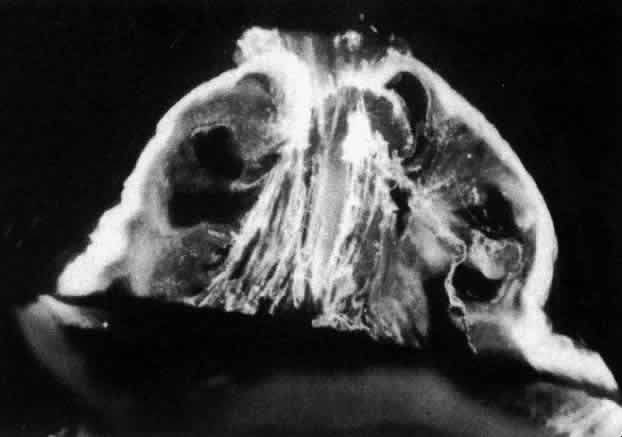

There are changes that occur in vitreous structure throughout life.82,92 Figure 8 demonstrates typical vitreous structure during late prenatal stages. Within the corpus vitreous there are no structures other than the remnants of the hyaloid artery oriented toward the prepapillary region. The corpus vitreous is relatively small and has an overall dense appearance with marked density at the outermost “shell” corresponding to the vitreous cortex. The generalized density of the corpus vitreous likely relates to the fact that at this stage of development, collagen and proteoglycan(s) other than HA are the principal structural components.62,79 HA synthesis begins after birth, increasing transparency by the aforementioned mechanisms.

Fig. 8. Vitreous morphology in human embryo. The posterior aspect of the lens is seen below. The corpus vitreous is enclosed by the dense, highly light-scattering vitreous cortex. Within the corpus vitreous, Cloquet's canal arcs from the prepapillary vitreous cortex toward the lens. Because its course undulates through the central vitreous, not all of Cloquet's canal can be visualized in a single horizontal section. (Sebag J: Age-related changes in human vitreous structure. Graefes Arch Clin Exp Ophthalmol 225:89, 1987)